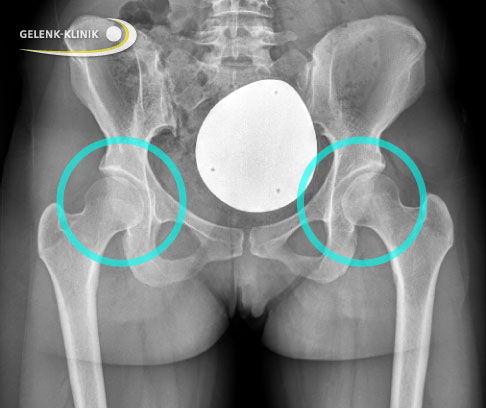

Bildgebende Untersuchung einer Hüftdysplasie bei Jugendlichen und Erwachsenen: Röntgen

Zur Abklärung eines Verdachts auf Hüftdysplasie bei jugendlichen oder erwachsenen Patienten fertigt der behandelnde Orthopäde röntgenologische Übersichtsaufnahmen des Beckens an. Er bewertet bei den Röntgenaufnahmen zwei Fragestellungen:

- Überdacht die Hüftpfanne den Hüftkopf ausreichend?

- Wie steht der Oberschenkelkopf im Gelenk?

Kann man eine Hüftdysplasie auf dem Röntgenbild erkennen?

Vor allem bei älteren Kindern und Erwachsenen kann man die Hüftdysplasie meist sehr gut im Röntgenbild erkennen. Die Hüftpfanne ist zu wenig ausgebildet und der Hüftkopf steht nicht zentriert in der Mitte der Pfanne. Häufig verschiebt sich der Hüftkopf auch nach außen oben. Der Schweregrad der Dysplasie kann zudem im Röntgenbild mit verschiedenen Winkeln bestimmt werden. Bei Säuglingen ist die Verknöcherung noch wenig fortgeschritten, deshalb ist bei ihnen zum Erkennen der Hüftdysplasie der Ultraschall überlegen.